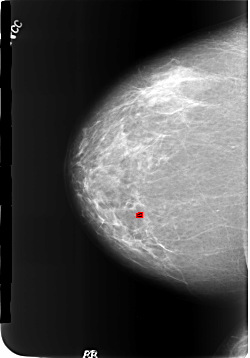

B_3186_1.RIGHT_CC

RIGHT_CC LINES 5720 PIXELS_PER_LINE 3992 BITS_PER_PIXEL 12 RESOLUTION 50 OVERLAY

FILE: B_3186_1.RIGHT_CC.OVERLAY

TOTAL_ABNORMALITIES 1

ABNORMALITY 1

LESION_TYPE CALCIFICATION TYPE LUCENT_CENTERED DISTRIBUTION N/A

ASSESSMENT 2

SUBTLETY 4

PATHOLOGY BENIGN

TOTAL_OUTLINES 1

BOUNDARY